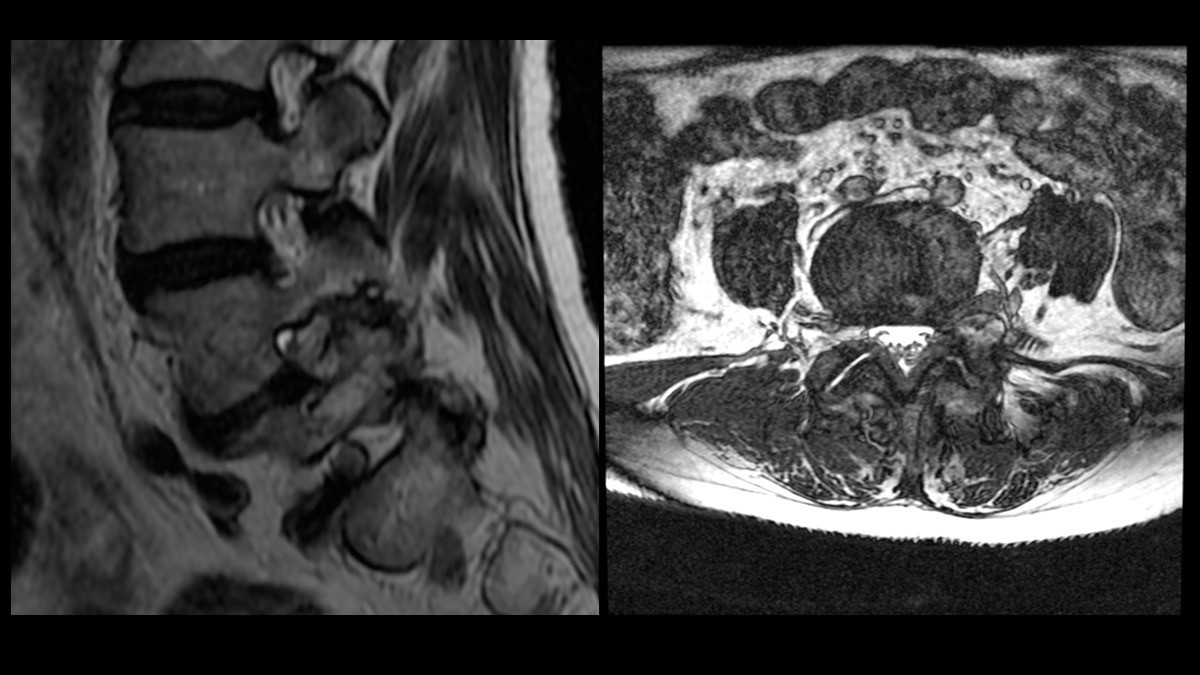

• Cirugías para problemas de columna, incluyendo microdiscectomía lumbar, una técnica mínimamente invasiva para tratar hernias de disco.

• Endoscopía de columna, una técnica avanzada para el tratamiento de problemas espinales.